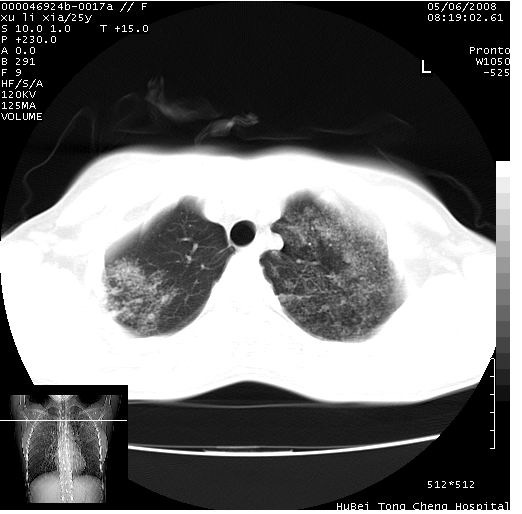

胸部ct轴位平扫(层厚10mm,螺距1.5,重建间隔10mm),图像如下:

(注:上级医院会诊胸部ct片——考虑为肺部真菌感染。)

病灶呈地图样分布于肺外围,与正常组织分界清晰+弥漫性磨玻璃影中见小叶间隔增厚呈碎石路样表现+年轻女性,无明显临床症状=肺泡蛋白沉积症?

病灶呈离心性分布,以两上肺多见,远离肺血管纹理,有部分肺间质条索影,病人症状轻微,考虑结节病。

平行于间质走行微结节影;拌钙化灶;分布通气好的肺野